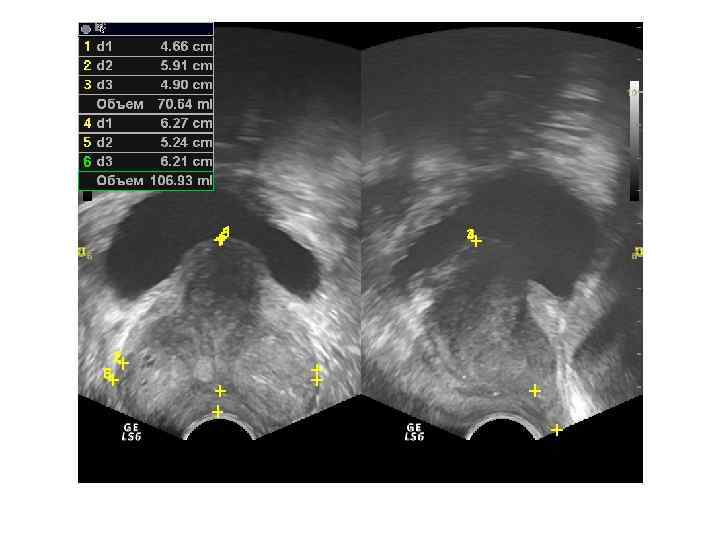

При ТРУЗИ объем простаты может быть определен с помощью нескольких методов: 1. Объем =А х В х С х 0, 52 (рис. 6. 5 А), где А — продольный размер, В — переднезадний размер, С — поперечный размер. Поперечный размер железы определяется при поперечном сканировании в ее средней части, переднезадний и продольный размеры — при сагиттальном сканировании 2. Объем = С 2 х В х 0, 52 где В — передне-задний размер, С — поперечный размер. 3. Объем = С 3 х 0, 52 где С — поперечный размер.

Нормальные размеры простаты